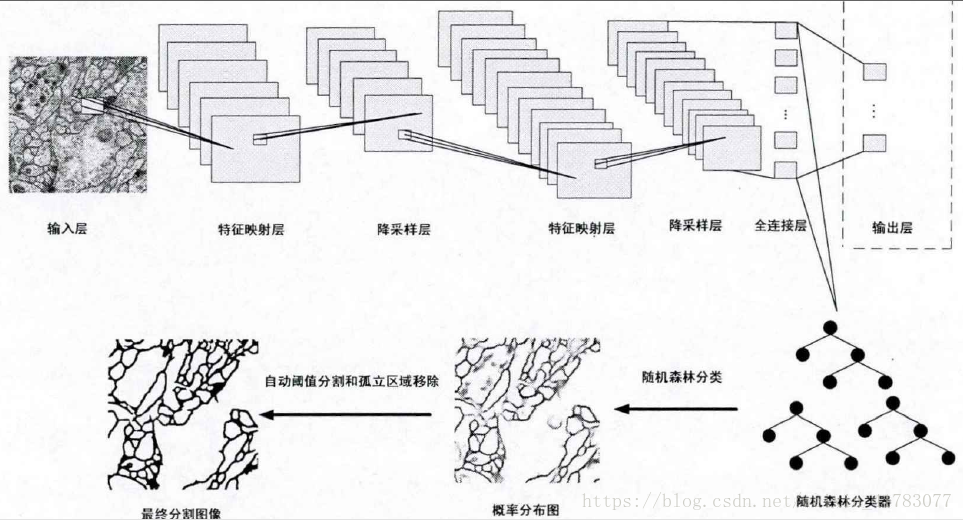

卷积神经网络不仅在处理医学影像辅助患者进行疾病诊断方面取得了巨大成功,在电子显微成像中对细胞膜分割方面同样有着积极的意义。文献[39][40]提出了基于卷积神经网络实现电子显微图像细胞膜自动分割的方法,方法中用卷积神经网络的监督训练去恢复patches中移除的中心像素标签,能够自动改善用于执行电子显微图像自动分割的细胞膜检测概率图。其中,patches是从细胞膜检测概率图中采样得到的,细胞膜检测概率图是通过分类器算法判断是否图像中的一个像素对应在细胞膜上得到。最后实验表明,相比于传统的机器学习算法,文献[39]方法性能有显著的提高,其结构如图15所示。

图15 深度神经网络监测细胞膜

在文献[40]中又提出了基于迭代的卷积神经网络的细胞膜分割方法,通过在细胞膜检测概率图上迭代地使用卷积神经网络算法,细胞膜分割结果又有了一定的提升。文献[41][42]提出了用卷积神经网络和随机森林相结合的方法实现了对神经细胞图像的分割,这两种方法均获得了优良的分割性能,但他们的侧重点有些不同。文献[41]中对传统的卷积神经网络模型进行了改进,如图16所示,用随机森林分类器代替了传统的softmax分类器。在整个模型中,分别训练卷积神经网络特征提取模型和分类器模型。卷积神经网络模型训练好之后,用其学习到的特征训练随机森林分类器,最后完成电子显微图像的神经细胞膜的分割。通过实验表明,分割准确度明显高于传统的分割算法SVM,而且用随机森林做分类器比用传统的softmax做分类器效果也要好一些。

图16 基于卷积神经网络和随机森林的细胞分割流程